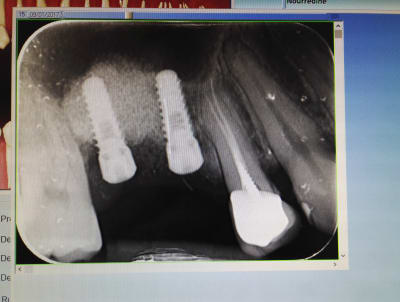

Bonsoir, pourriez-vous m'éclairer sur la marque de ces implants posés il y a 4 ans en France?

ETK ?

ETK Naturall